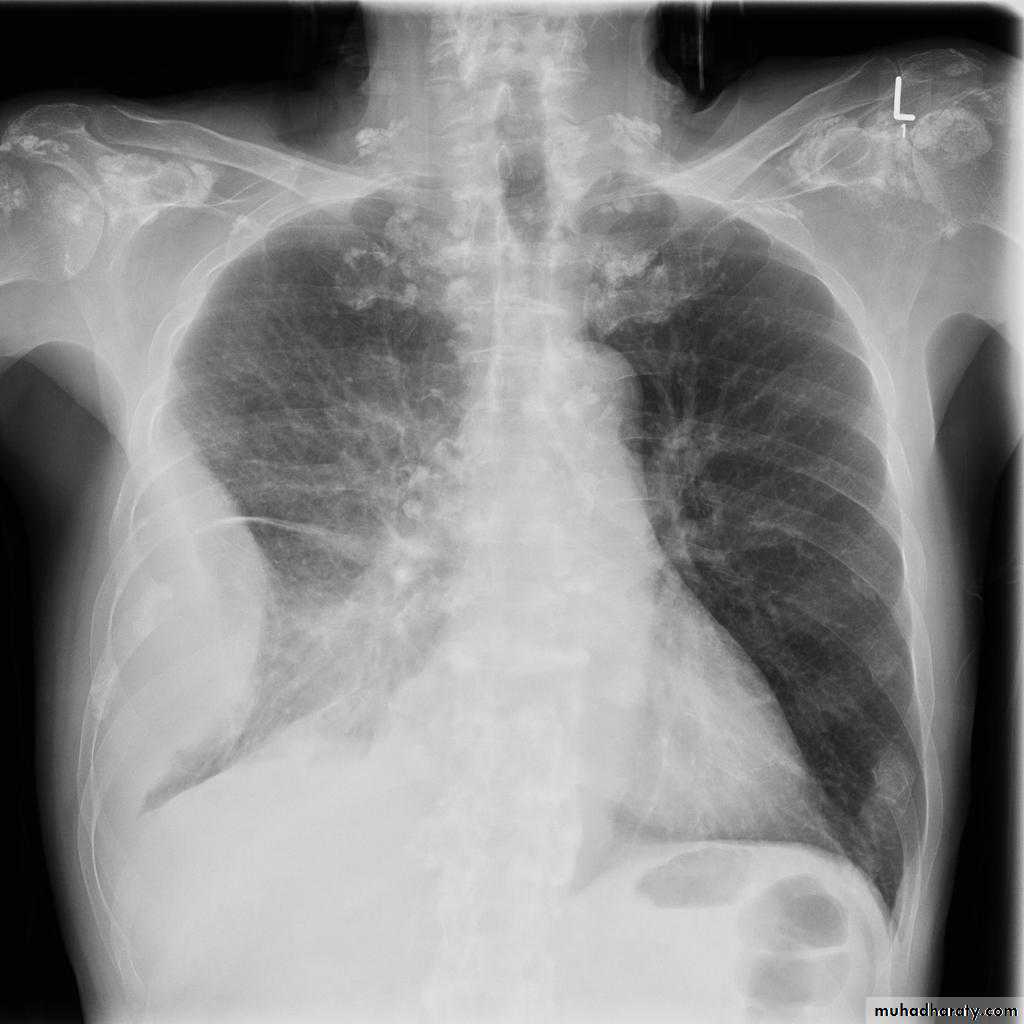

Post primary TB radiographic appearance

Post-primary pulmonary tuberculosis, also known as reactivation tuberculosis or secondary tuberculosis occurs years later, frequently in the setting of a decreased immune status. In the majority of cases, post-primary TB within the lungs develops in either :

* posterior segments of the upper lobes

*superior segments of the lower lobes

Typical appearance of post-primary TB

1.patchy consolidation or poorly defined linear and nodular opacities in both apices , upper zone in one lung , & lower zone in other lung ( ulternating lesion ) .2. Post-primary infections are far more likely to cavitate with multiple abscess formation & air fluid level more develop in the posterior segments of the upper lobes.

3. Tuberculomas seen in post-primary TB and appear as a well defined rounded mass typically located in the upper lobes .

4. Miliary tuberculosis is uncommon but carries a poor prognosis. It represents haematogenous dissemination of an uncontrolled tuberculous infection. It is seen both in primary and post-primary tuberculosis. Although implants are seen throughout the body, the lungs are usually the easiest location to the image. Miliary deposits appear as 1-3 mm diameter nodules . are uniform in size and uniformly distributed